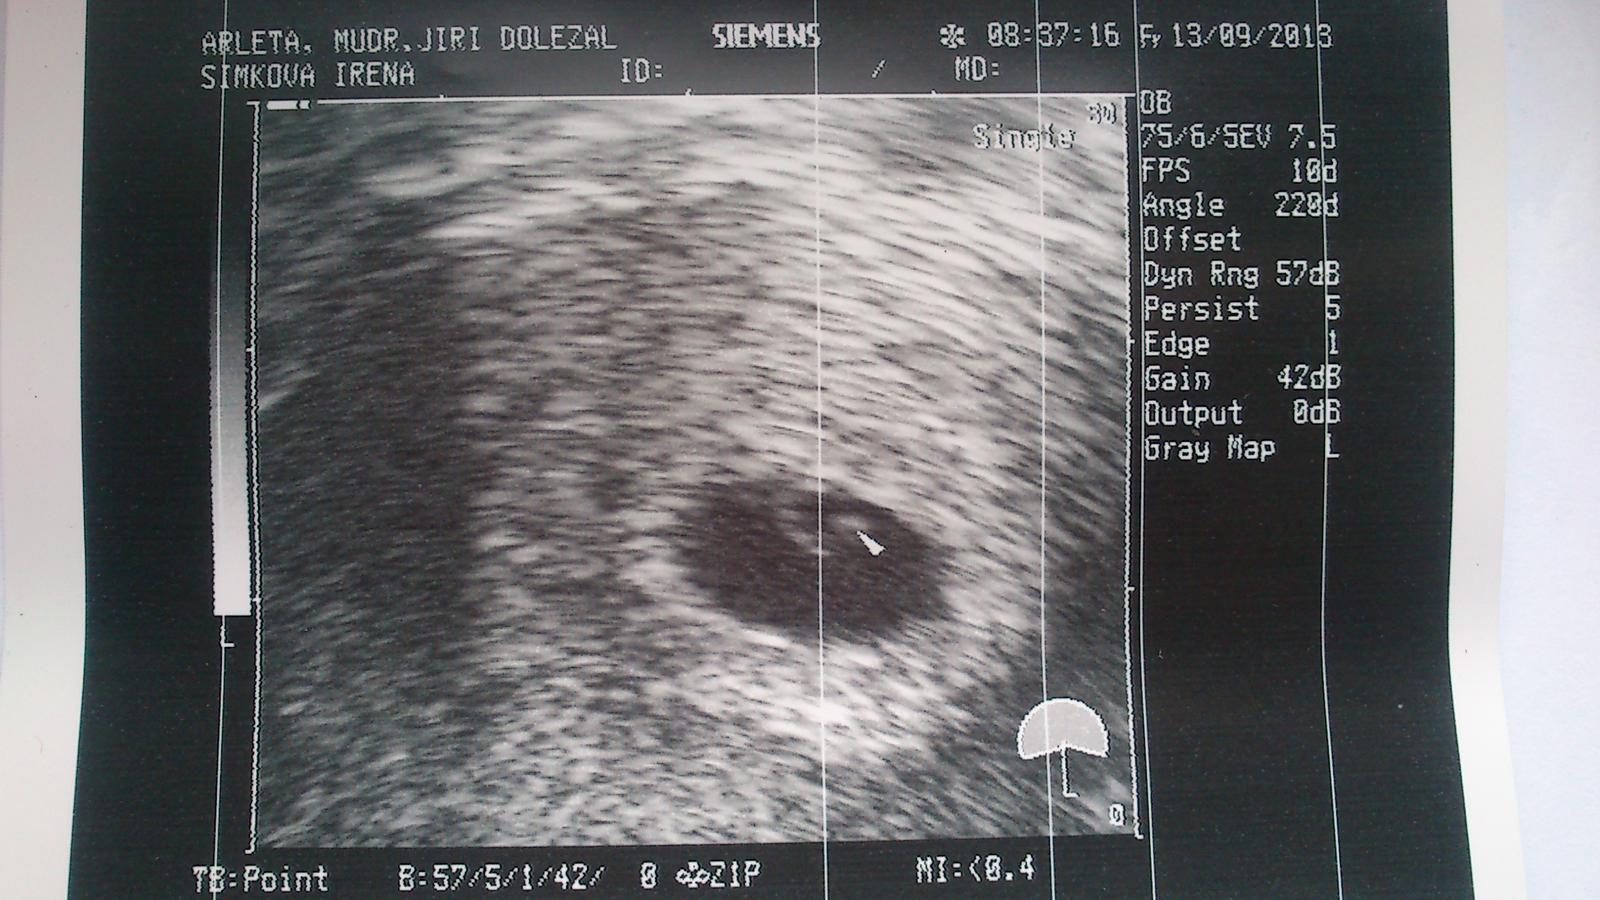

Ahoj kočenky. 🙂 Tak mimísek na utz je jeden a podle zprávy odpovídá 5+3,jinak jsme asi 5+4.Pan doktor říkal,že už vidí i srdíčko,ale já ho ještě pořádně neuvidím. 🙂 Je to na první fotečce ta šipečka.Jinak kontrola za 14 dní,to už dostanu i těhu průkazku a budou mi dělat odběry na prvotrimestrální screening.To zas bude nekonečných 14 dní......................... 😅 😅 😅 😅